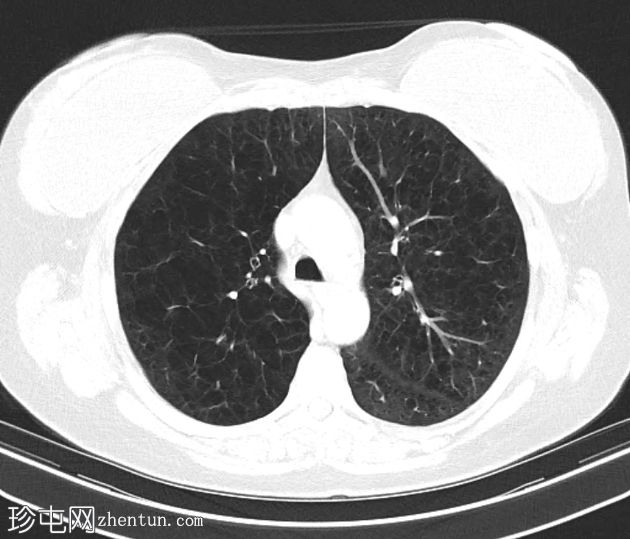

双侧肺(尤其是上叶)广泛融合性小叶中心型肺气肿。

左上叶肺瘢痕形成,可能是先前感染的后遗症。

双侧乳房植入。

早期小叶中心性肺气肿通常表现为小(<1 mm 至 3 cm)、圆形、均匀分布、边界不清的透亮区,可能出现在小叶中心动脉周围的次级肺小叶中央部分,而在严重的情况下,低衰减区会融合且不可分离,并且失去小叶中心分布。